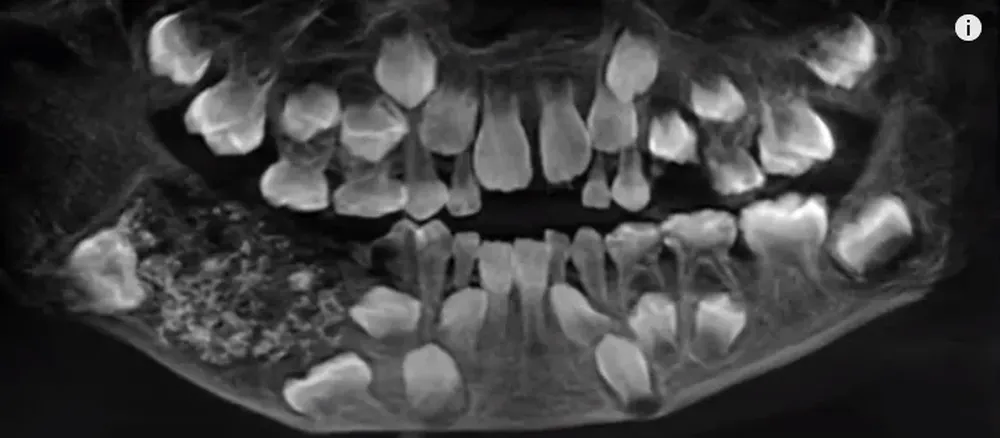

El mes pasado el niño fue ingresado al hospital por hinchazón y dolor cerca de sus muelas en la mandíbula inferior derecha. Cuando los médicos le hicieron una placa en la boca encontraron incrustados, en su mandíbula inferior, "dientes anormales", dijo a CNN el médico Prathiba Ramani.

Los médicos necesitaron examinar de forma individual cada diente antes de poder confirmar los hallazgos, aunque la cirugía, que tardó entre cuatro y cinco horas, se realizó el mes pasado.

"Había un total de 526 dientes que iban desde 0,1 milímetros a 15 milímetros. Incluso la pieza más pequeña tenía una corona, raíz y capa de esmalte que indicaban que era un diente", dijo Ramani. El niño fue liberado tres días después de la cirugía y se espera que se recupere por completo, agregó el médico.

Ramani dijo que el niño padecía "odontoma compuesto", una condición muy rara, y agregó que la causa de la afección no está clara, pero podría ser genética o podría deberse a factores ambientales como la radiación. El niño en realidad puede haber tenido los dientes extra por algún tiempo. Sus padres les dijeron a los médicos que habían notado una hinchazón en su mandíbula cuando tenía 3 años, pero no pudieron hacer mucho al respecto porque no se quedaría quieto ni permitiría que los médicos lo examinaran.